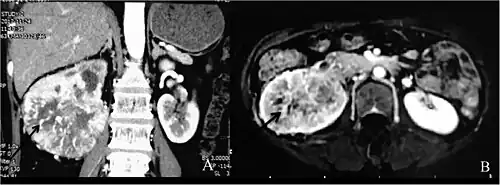

Individuals with Dioctophyme renale infection (known as dioctophymosis) typically present with unspecific symptoms including hematuria[1][3] (blood in urine), nephritis, loin pain,[7] renal enlargement, and/or renal colic[1] (intermittent pain in the kidney area), which may result from the rare migration of worms through ureters.[5][7][1][3] In some cases the fibrosis occurring after parasite infection is an incidental finding in ultrasound or CT scan, mimicking renal cancer, leading to radical nephrectomy.[11]